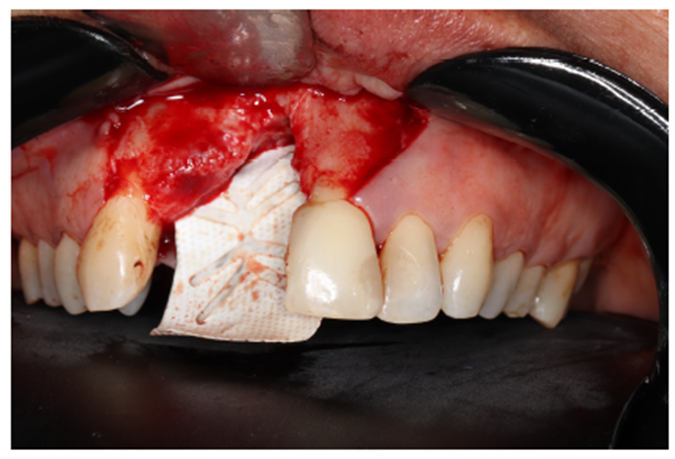

Após a descorticalização, a membrana de PTFE-d (Cytoplast) foi aberta para modelagem e adaptação no rebordo, visando o acomodamento do material de enxertia. Ela foi parafusada na cortical palatina facilitando a inserção do material via vestibular. (Figuras 5 e 6).

Após o preparo do tecido mole, foram colocadas membranas de L-PRF sobre as membranas de PTFE-d com o intuito de auxílio na reepitelização da cicatrização cirúrgica.

A escolha do fio é de extrema importância para o sucesso da cirurgia. Foi utilizado o fio de sutura de PTFE Cytoplast, cuja elasticidade acompanha o edema pós-operatório, diminuindo o risco de deiscência de sutura (Figuras 10 e 11).